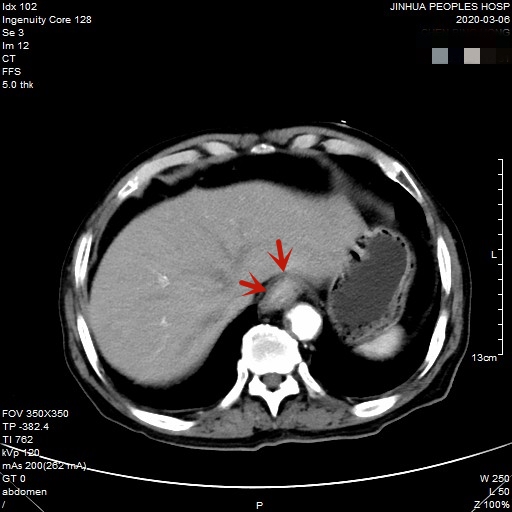

医生予以进一步检查CT增强发现肿瘤倒是没有明显侵犯周围脏器或结构,请我去会诊后,仔细阅片,发现从影像上看还是能够根治性切除的。所以转来胸外科拟进一步行手术治疗。下面是其CT增强的图像:

以上图片红色箭头所指处为贲门部肿瘤